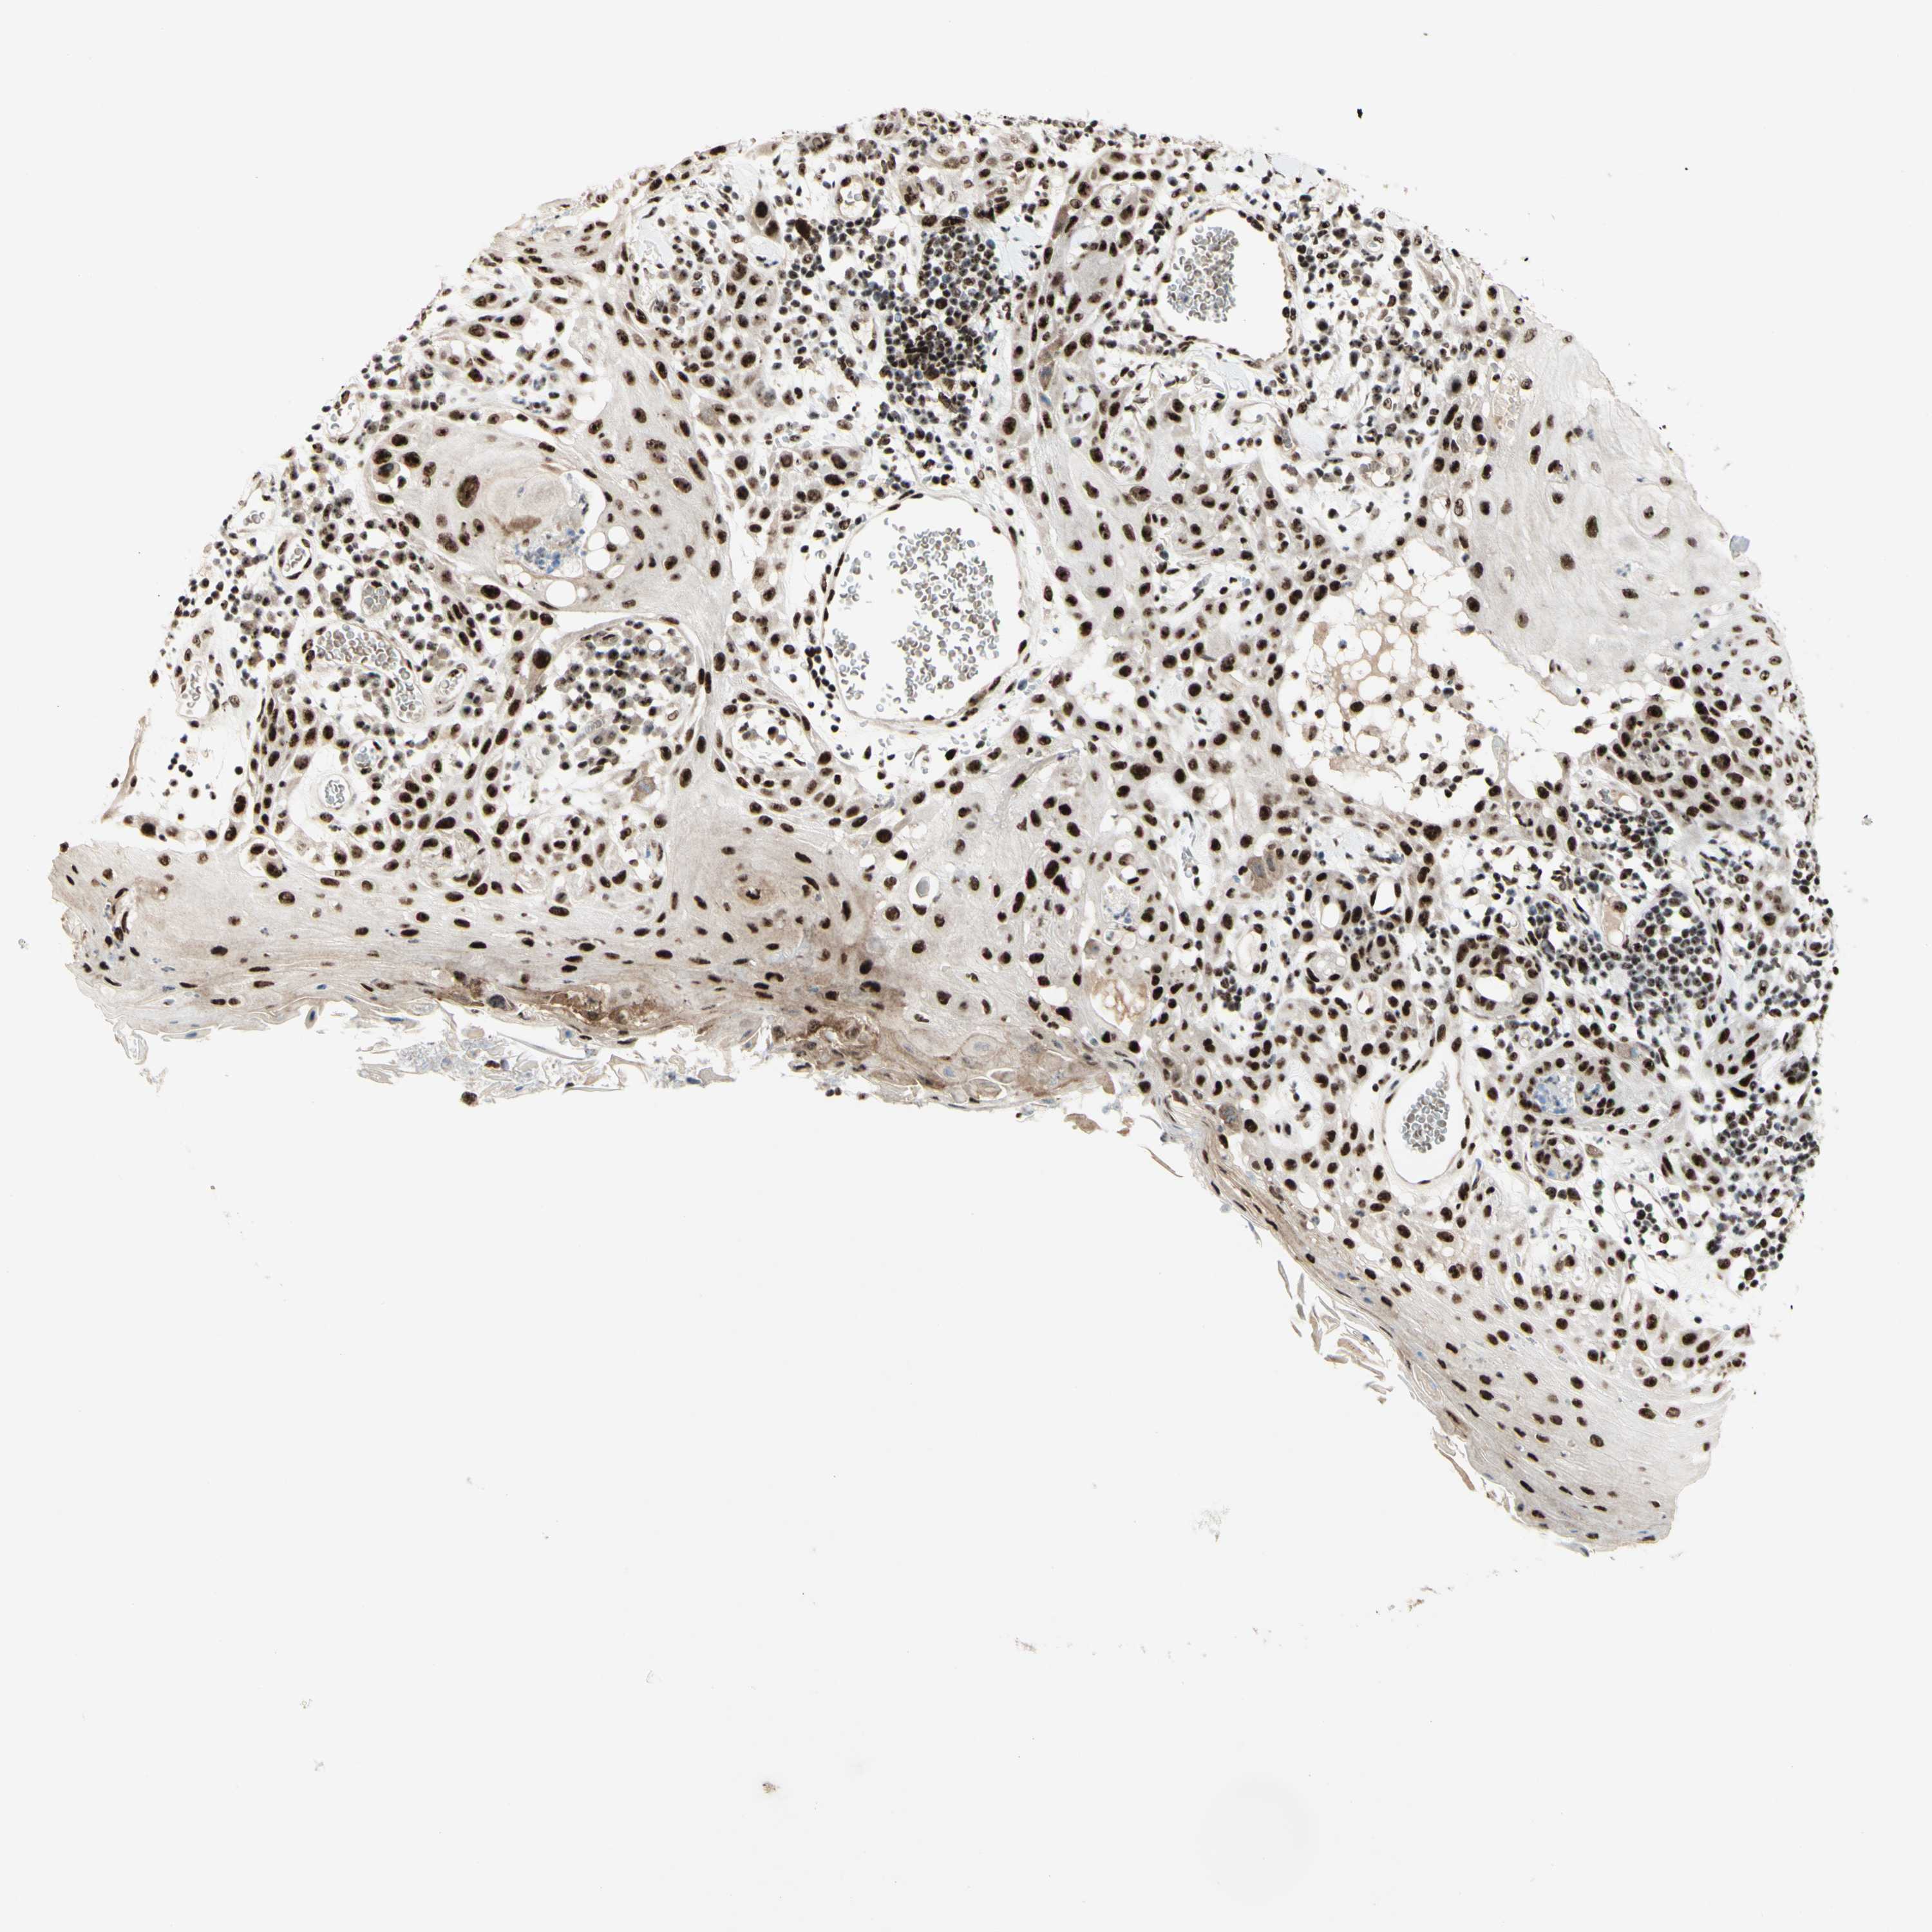

SKIN CANCER - Protein expressioni

A mouse-over function shows sample information and annotation data. Click on an image to view it in a full screen mode. Samples can be filtered based on level of antibody staining by selecting one or several of the following categories: high, medium, low and not detected. The assay and annotation is described here.

Each image is clickable and will lead to virtual microscopy that enables deeper exploration of all samples and also displays staining intensity scores, fraction scores and subcellular localization as well as patient and tissue information for each sample.

Antibody HPA028050

Staining

High

Intensity

Strong

Quantity

>75%

Location

Nuclear

Basal cell carcinoma